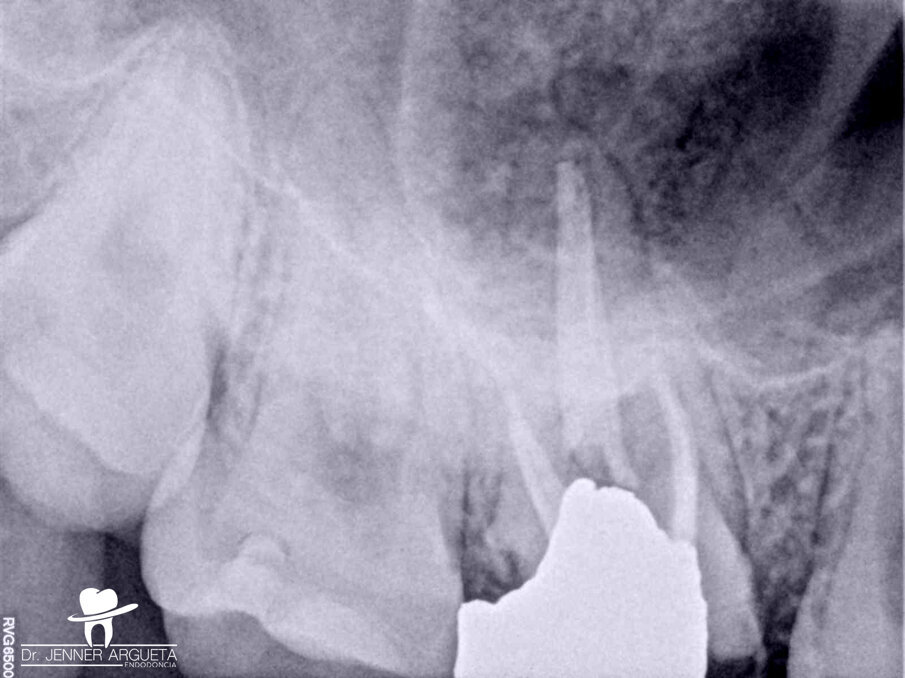

A 16-year-old female patient was referred to the office for evaluation of tooth #16 (Fig. 1). The referring dentist asked that we apply all the available resources to save the tooth. The diagnosis was previously treated and symptomatic periapical periodontitis. After detailed examination, it was concluded that the tooth was not restorable. With the parents’ and patient’s agreement, we decided on an autogenous transplantation of tooth #18 to the site of tooth #16 after its extraction (Fig. 2). The orthodontist had determined that tooth #18 was to be extracted, and it was intended that the patient’s occlusion should be balanced by the end of the orthodontic treatment. Teeth #16 and 18 were extracted in the least traumatic way possible. After minor bone remodelling of the socket using low-speed burs, the third molar was transplanted to the recipient site (Fig. 3). A nylon monofilament flexible splint was used to keep the tooth in place (Fig. 4). Fifteen days later, the splint was removed, healthy soft tissue was observed, the patient was asymptomatic, and the tooth was stable in the site (Figs. 5a & b).

Fig. 2: Periapical radiograph of the maxillary right molar. Tooth #18 was to be transplanted to the site occupied by tooth #16.